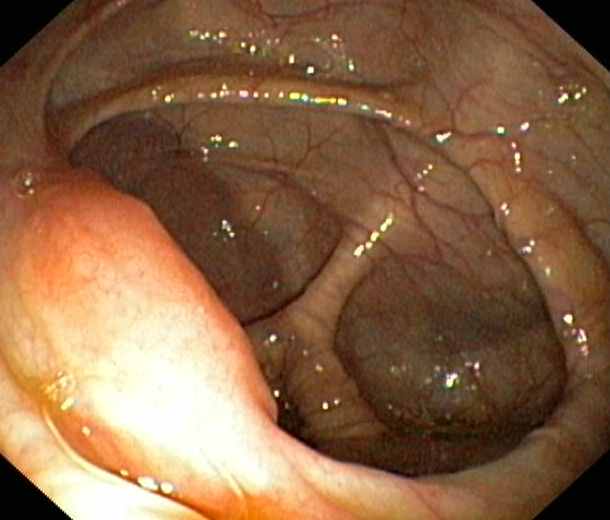

Ileocaecal valve